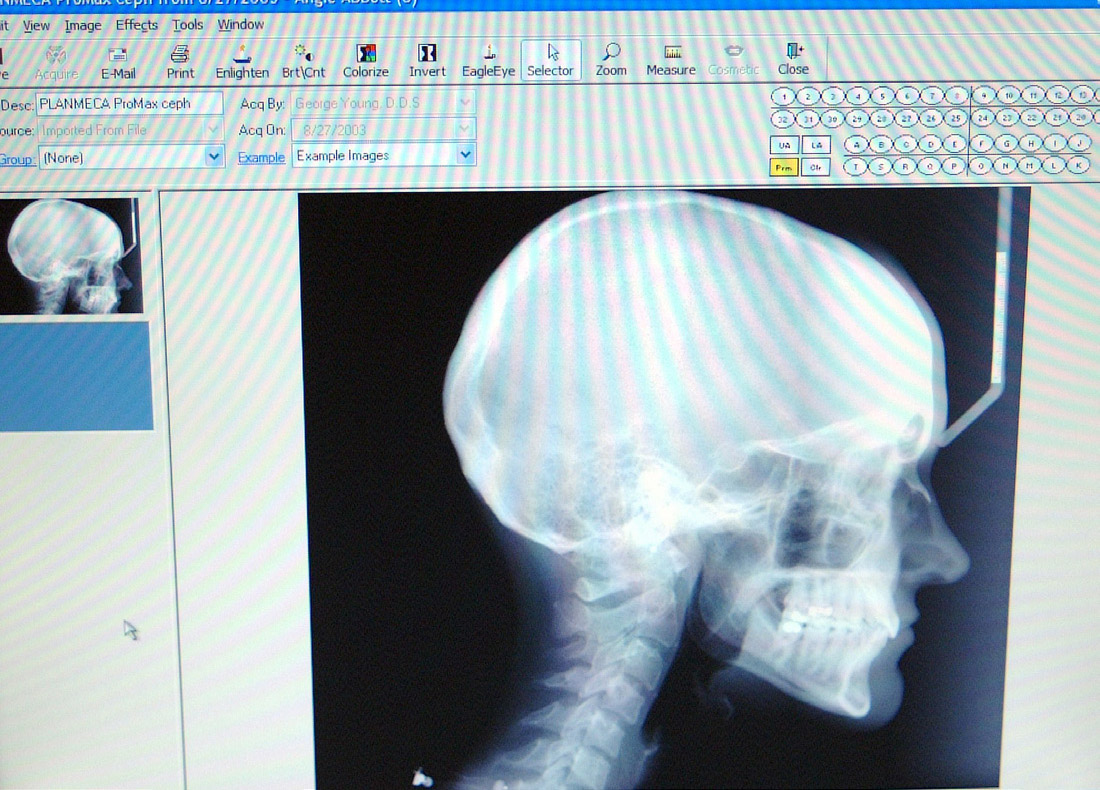

Figure 5. A digital extraoral radiographic image is displayed on the computer monitor. This particular radiographic projection is a lateral head plate. (Patterson Dental Supply, Inc)

Figure 5

As with intraoral digital radiography, extraoral digital images can be acquired using direct or indirect digital imaging systems. Digital panoramic and cephalometric machines are available that utilizes either linear array CCD or CMOS detectors or PSP plate sensors. With CCD or CMOS extraoral imaging, conventional film is replaced by a long, vertical, rigid digital receptor a few pixels wide.31 With PSP receptors, the plate is configured in the same dimensions as panoramic or cephalometric film and can be placed directly into the cassette with the intensifying screens removed. As with intraoral direct digital imaging, a patient file must be created, the appropriate template or projection selected, patient positioned, exposure made, and image viewed on the monitor (Figure 5). With PSP plate receptors, the plate needs to be scanned before the image can be viewed. The technique for preparing and positioning the patient is similar to conventional panoramic and cephalometric radiography. In addition, errors can be produced when the patient is improperly prepared and the head alignment does not conform to technique requirements. The quality of the resulting image is ultimately the responsibility of the clinician and proper application of extraoral imaging techniques.

Both film-based and digital formats produce comparable images with spatial resolution of 3 lp/mm to 4 lp/mm for PSP receptors and 6 lp/mm to 8 lp/mm for CCD receptors.32 As with intraoral digital imaging, elimination of the darkroom, the ability to enhance9 and analyze the image,33 and the convenience of image storage, duplication, and retrieval are beneficial. With extraoral imaging, the file size is considerably larger than intraoral imaging and must be reduced by compression techniques that facilitate stor­age but do not compromise the diagnostic quality of the image.